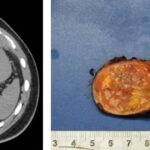

Se presenta el caso de un paciente masculino de 18 años sin antecedentes, que consulta por dolor en hipocondrio derecho de un año de evolución, asociado a palpitaciones, y episodios de HTA. El examen de orina de 24 horas mostró niveles elevados de catecolaminas. En la ecografía abdominopélvica y TAC abdominal, se objetiva una formación de aspecto nodular sólida hipoecoica de contornos bien delimitados, de aproximadamente 43 mm x 39 mm, que no muestra vascularización a la señal Doppler color, asociado a la TC abdomen con contraste EV: masa sólida de 38 mm x 31 mm, reemplazando el parénquima de la glándula suprarrenal derecha que realza de forma ávida y heterogénea en fase arterial a expensas de área central con degeneración necrótica. Se prepara con alfa bloqueador, se realiza adrenalectomía total izquierda laparoscópica. La anatomía patológica evidencia feocromocitoma.

El feocromocitoma es una entidad que afecta a pacientes jóvenes y tiene diversos hallazgos imagenológicos, siendo los más característicos por ecografía como masas grandes sólidas o quísticas con calcificaciones, de bordes bien definidos, dependiente de una glándula suprarrenal, en la TAC suelen ser heterogéneas, frecuente la calcificación, hemorragia y necrosis, con marcado realce tras la administración de contraste. Siendo este el gold standard con el protocolo de lavado suprarrenal se compone de una fase sin contraste, una exploración contrastada con un retraso de 60-90 segundos y una tardía a los 15 minutos con densidad > 10UH.